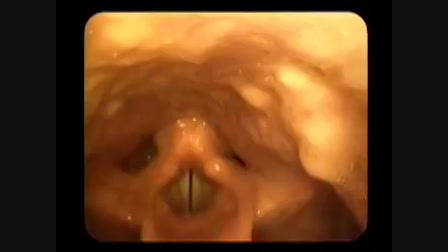

Van nekem egy anyosom.